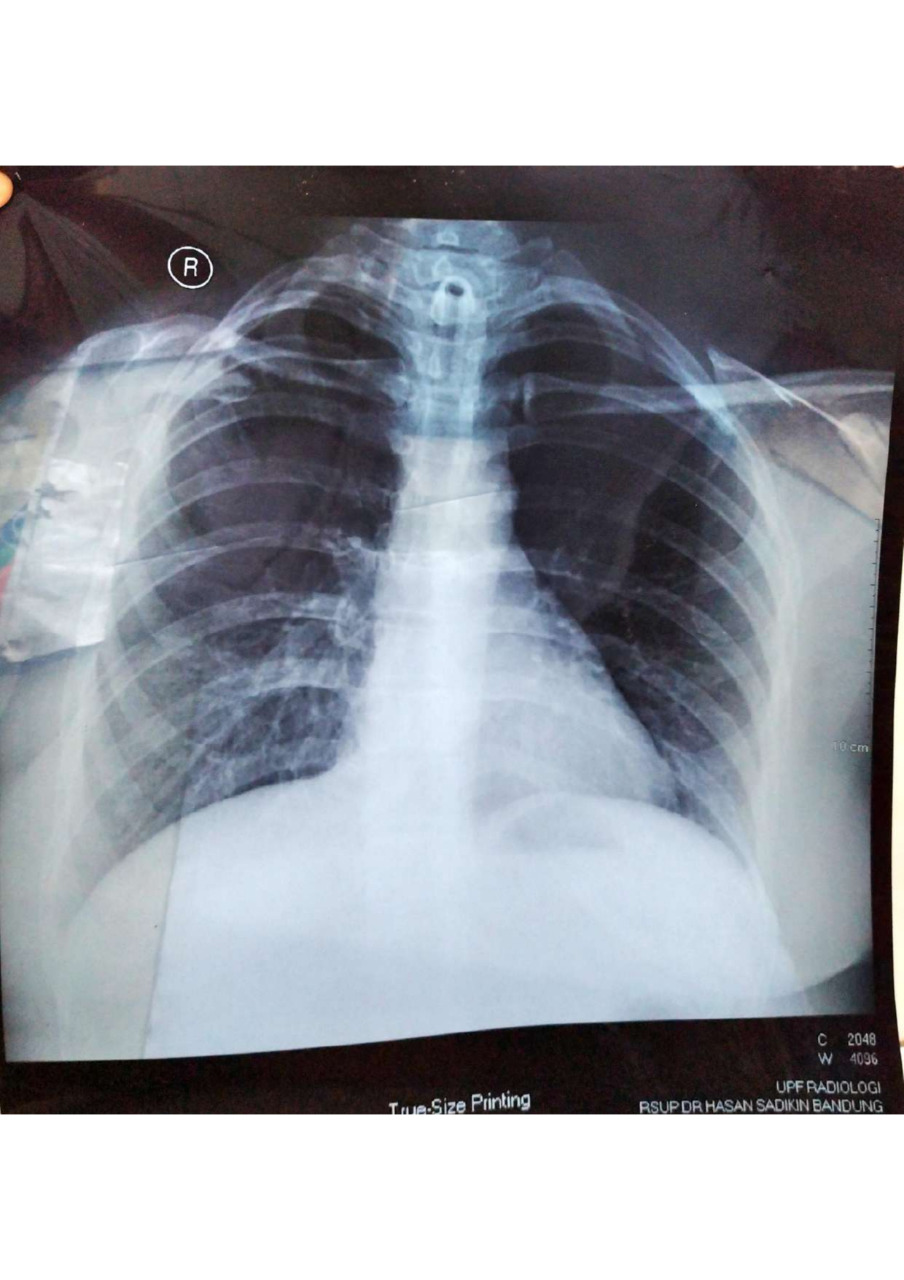

Akibat dari kecelakaan itu, dokter mendiagnosis Bu Rosyidah tidak bisa berbicara dan napas melalui hidung, sehingga harus dialihkan ke tenggorokan dengan menggunakan alat trakeostomi yang dipasang di lehernya.

Kami dari Yayasan Bina Suluk Rahayu mengucapkan terima kasih sebesar-besarnya atas bantuan dan dukungan yang telah diberikan #TemanBaik untuk Ibu Rosyidah yang mengidap stenosis laring dan subglotis, semoga kebaikan dan rezeki kalian semua dilipat gandakan serta menjadi berkah.